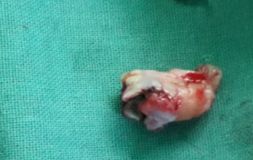

The tooth removal process depends upon the stage in which the wisdom teeth is. It is easy to extract wisdom tooth if it has fully erupted. But if the tooth is impacted then it will require an incision in the gums. Usually, the tooth is extracted in parts to minimize the amount of bone required to be extracted for tooth removal.